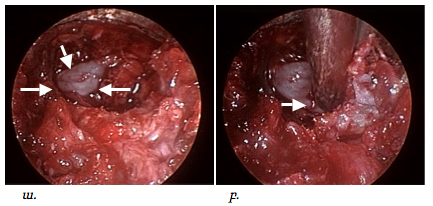

Կատարված գործողություններից հետո հայտնաբերվում էր ողի աղեղը, այն շերտազատվում էր փափուկ հյուսվածքներից աքցանների և էլեկտրոկոագուլիացիայի օգնությամբ, որից հետո բարձր արագության պնևմատիկ շաղափիչի օգնությամբ շաղափվում էր ողի աղեղի մի մասը: Եթե հիվանդի մոտ առկա էր նաև ֆորամինալ ստենոզ, պայմանավորված ելունային հոդի գերաճով, ապա վերջինս հեռացվում էր (pars superior articularis), ինչը պատկերված է նկար 4-ում:

Նկ. 4 Ներվիրահատական էնդոսկոպիկ նկար

ա. Փափուկ հյուսվածքներից շերտազատված ելունային հոդ

բ. Ողի աղեղի շաղափման փուլ

Ոսկրային պատուհան ձևավորելուց հետո նրա շրջագիծը լայնացվում էր ոսկրակրծիչների օգնությամբ մոտ 1.5-2.0սմ /փաստացի կատարվում էր էնդոսկոպիկ հսկողությամբ հեմիլամինէկտոմիա/: Այս գործողությունների ընթացքումպահպանվում էր դեղին կապանի ամբողջականությունը, ինչըայս փուլի ժամանակ կրում էրպաշտպանիչ ֆունկցիա՝ կանխարգելելով կարծրենու հնարավոր վնասումըշաղափով կամ ոսկրակրծիչներով: Ոսկրային պատուհանի ձևավորումը ցույց է տրված նկար 5-ում:

Նկ. 5 Էնդոսկոպիկ հսկողությամբ ոսկրային պատուհանի ձևավորման փուլ

ա. մասնակի ոսկրային դեֆեկտը շաղափելուց հետո (ցույց է տրված սլաքով)

բ. Ձևավորված ոսկրային պատուհան, միևնույն ժամանակ պահպանված է դեղին կապանի ամբողջականությունը (ցույց է տրված սլաքով)

Հաջորդ փուլը համարվում էր վիրահատության ամենակարևորը: Այս ժամանակ կատարվում էր դեղին կապանի շերտազատում կարծրենուց: Վերջինս կատարվում էր գնդիկաձև ծայր ունեցող կեռիկի օգնությամբ: Այս գործողությունների ժամանակ կարևոր էր խուսափել կարծրենու վնասումից կամ էլ էպիդուրալ երակային ցանցի վնասումից, որի արյունահոսությունը դժվարությամբ էր ենթարկվում կանգնեցման: Սկզբից բացազատվում էր կարծրենին մեդիալ ուղղությամբ՝ հասնելով միջին գիծ, որից հետո հետադարձ գործողություններով բացազատվում էր ողնաշարային խողովակի լատերալ սահմանը, հայտնաբերվում էր նյարդարմատը և վերջինս շերտազատվում էր կոմպրեսիա առաջացնող հյուսվածքներից մոտ 1.5սմ երկարությամբ, ինչը պատկերված է նկար 6-ում:

Նկ. 6 Կարծրենու շերտազատման փուլ

ա. Կարծրենին բացազատված է մեդիալ ուղղությամբ (ցույց է տրված սլաքով)

բ. Բացազատված է ճնշված նյարդարմատիկը (ցույց է տրված սլաքով)